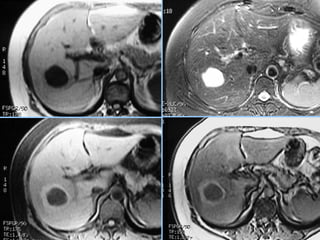

► s/c: Massa esférica, iso ou hipodensa (devido ao conteúdo lipídico).

Hemorragia: áreas hiperatenuantes intra-tumorais, parenquimatosas

ou subcapsulares.

Pode haver gordura ou calcificações.

► c/c:

– Fase Arterial: Realce intenso (< q na HNF) e heterogêneo

– Fase Portal: Diminuição da atenuação e da heterogeneidade do realce.

– Fase Tardia: Isodenso ao parênquima. Realce não persiste.

Adenoma Hepático

 Fase art.    Fase portal    Fase tardia

 S/C                Fase arterial

 Fase portal        Fase tardia